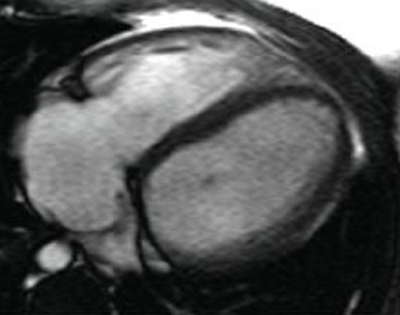

Magnetic resonance imaging (MRI) in a patient with pulmonary regurgitation following repair of tetralogy of Fallot. The patient has a restrictive right ventricle, and MRI shows decreased right ventricular volume

From: Chaturvedi RR, Redington AN. Heart. 2007 Jul;93(7):880-9; used with permission